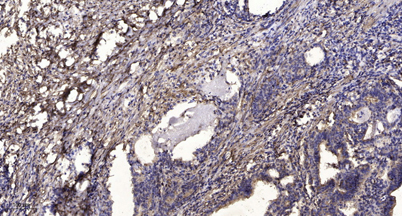

Immunohistochemical analysis of paraffin-embedded human Gastric adenocarcinoma. 1, Antibody was diluted at 1:200(4° overnight). 2, Tris-EDTA,pH9.0 was used for antigen retrieval. 3,Secondary antibody was diluted at 1:200(room temperature, 45min).